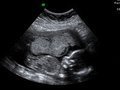

Оплодотворение, слияние мужской половой клетки (сперматозоида) с женской (яйцом, яйцеклеткой), приводящее к образованию зиготы — нового одноклеточного организма. Биологический смысл оплодотворения состоит в объединении ядерного материала мужской и женской гамет, что приводит к объединению отцовских и материнских генов, восстановлению диплоидного набора хромосом, а также активации яйцеклетки, то есть стимуляции её к зародышевому развитию. Соединение яйцеклетки со сперматозоидом обычно происходит в воронкообразно расширенной части маточной трубы в течение первых 12 часов после овуляции. Семенная жидкость (сперма), попадая во влагалище женщины при половом сношении (коитусе), обычно содержит от 60 до 150 млн сперматозоидов, которые благодаря движениям со скоростью 2 — 3 мм в минуту, постоянным волнообразным сокращениям матки и труб и щелочной среде уже спустя 1 — 2 минуты после полового акта достигают матки, а через 2 — 3 часа — концевых отделов маточных труб, где обычно и происходит слияние с яйцеклеткой.

Многие сперматозоиды, находящиеся в половых путях женщины, могут сохранять способность к оплодотворению 48 — 72 часа (иногда даже до 4 — 5 суток). Овулировавшая яйцеклетка сохраняет жизнеспособность примерно 24 часа. Учитывая это, наиболее благоприятным временем для оплодотворения считается период разрыва созревшего фолликула с последующим рождением яйцеклетки, а также 2 — 3-й день после овуляции. Женщинам, применяющим физиологический метод контрацепции, следует помнить о том, что сроки овуляции могут колебаться, а жизнеспособность яйцеклетки и сперматозоидов может быть значительно больше. Вскоре после оплодотворения начинается дробление зиготы и образование зародыша.

В последние годы для лечения бесплодия применяется метод экстракорпорального оплодотворения — оплодотворение яйцеклетки человека вне организма, культивирование её до определённой стадии и перенос эмбриона (зародыша) в матку. Абсолютным показанием для этого метода оплодотворения является трубное бесплодие, которое развивается вследствие непроходимости или отсутствия маточных труб. В случаях мужского бесплодия применяют инструментальное введение в половые пути женщины спермы мужа или донора с целью обеспечения у неё зачатия (см. Инсеминация искусственная).